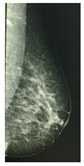

According to the Breast Imaging Data and Reporting System (BI-RADS), a PBD increase along a three-year period is associated with a higher breast cancer risk, and a PBD decrease with a smaller risk, than the risk when PBD remains unchanged. Two longitudinal BI-RADS breast density measurements (on current and previous mammography) may be better predictors of breast cancer risk than a single measurement [14]. The incorporation of breast density to the Gail model, a mathematical instrument that measures the risk of developing breast cancer in five years by identifying risk factors [15], increases predictive accuracy by statistical agreement from 0.607 to 0.642 [16]. The PBD BI-RADS classification is defined in Table 1, where illustrative cranio-caudal (CC) and mid-lateral oblique (MLO) mammography imaging samples for right and left breast are shown.

Table 1. BI-RADS classification and its relationship with mammography.

BI-RADS PBD ClassificationMammography

Right

(CCR)

Left

(CCL)

(MLOR)

(MLOL)

a = 0–25%

(Homogeneous adipose)

Sensors 22 02747 i001 Sensors 22 02747 i002 Sensors 22 02747 i003 Sensors 22 02747 i004